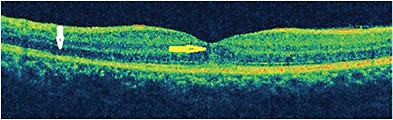

Dome-shaped hyperreflective lesions in the region of dots in the subretinal space are seen on OCT, along with attenuation and disruption of the IS/OS junction. Increased reflectivity of the choroid beneath the lesions has been observed and is due to inflammatory aggregates. The hyperreflective lesions correlated with the subretinal dots resolve, and the IS/OS junction slowly is restored.7,23 The photoreceptor cell bodies are always intact, permitting complete recovery of the photoreceptor outer segments.16 In recurrent MEWDS, the outer nuclear layer (ONL) thins, suggesting that recurrent MEWDS can lead to photoreceptor atrophy.24

Spectral-domain OCT shows dome-shaped hyperreflective material on the RPE extending to the inner retina through disruption of the EZ, interdigitation zone (IZ), and ONL (Figure 4).6 Irregularities of the RPE have been reported. Extrafoveal lesions corresponding to dots and spots show disruption of the EZ and IZ. Peripapillary fluid can be seen as a hyporeflective accumulation or as a pigment epithelial detachment on OCT that can progress to peripapillary atrophy following resolution of MEWDS.19,25 In the hyper early stage of MEWDS, the RPE layer is shown to be split with intact EZ, IZ, and external limiting membrane (ELM) in the perimacular area. The ellipsoid zone is shown to be disrupted in the peripapillary zone corresponding to hyperautofluorescent lesions on OCT. Spectral-domain OCT shows subfoveal hyperreflective lesion with disruption of EZ, IZ, and ELM. All of these changes are shown to resolve with disease resolution.17